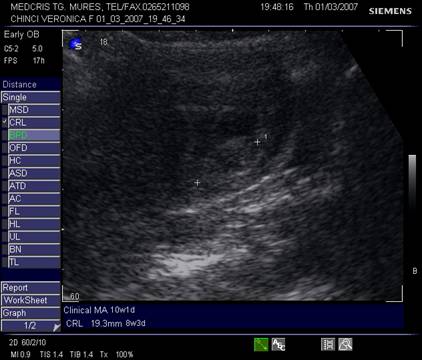

Fig nr.83 Discrepanta dintre lungimea cranio caudala embrionara (CRL intre calipere) ce corespunde la 8 saptamani si amenoreea de 12 saptamani, se remarca absenta veziculei viteline

Fig nr. 84. Discrepanta intre CRL (crown rump lenght sau lungimea craniocaudala)

si amenoree, la o sarcina oprita in evolutie